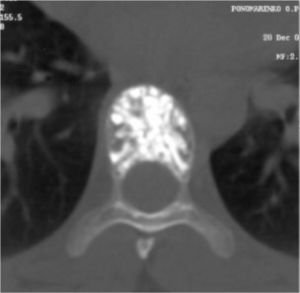

Рис.№ 2. КТ Th7 позвонка. Поражение гемангиомой всего тела Th7 позвонка.

Рис. №3. КТ Th9 позвонка. Поражение гемангиомой части тела Th7 позвонка.